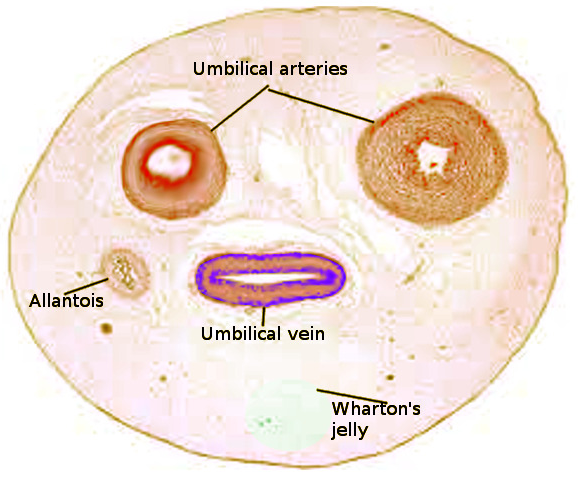

Động mạch dây rốn có thể trở thành nguồn triển vọng để phát triển các SDVG. Thông thường, dây rốn chứa 1 tĩnh mạch và 2 động mạch, được bao bọc bởi một lớp bảo vệ được gọi là Wharton’s Jelly (Hình 3). Đường kính động mạch trung bình tăng từ 1,2 ± 0,4 mm khi trẻ được 16 tuần lên mức 4,2 ± 0,4 mm ở thời điểm sinh. Đối với tĩnh mạch, đường kính trung bình đạt mức 2,0 ± 0,6 mm ở thời điểm 16 tuần và tăng tên 8,2 ± 0,8 mm ở thời điểm sinh. Hơn nữa, động mạch dây rốn có kích thước, cấu trúc các lớp thành mạch tương đồng với động mạch vành, khả năng chun giãn lớn, dễ lấy, không xâm lấn, cùng với đặc tính tái cấu trúc nên về lý thuyết, nguồn mạch này rất khả thi để thay thế cho các mạch máu nhỏ.